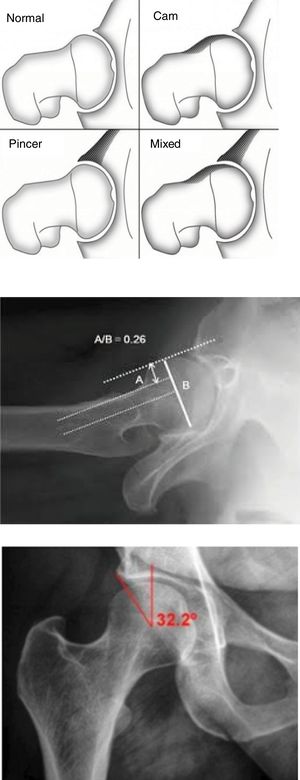

Femoroacetabular impingement or shock (FAI) is a recognised cause of coxalgia resulting from abnormal contact between the femur and the acetabulum, causing pain, limitation of movement and early osteoarthritis in the hip joint.1 Two types of impingement have been described depending on the predominant bone disorder. The cam type, due to femoral head asphericity, and the pincer type, caused by acetabular overcoverage or retroversion;2 mixed forms being the most frequent in terms of presentation (Fig. 1A). The aetiology of this syndrome is not clear, but morphological alterations of the developing femur, caused by the practice of sports or hypermobility of the hip joint, and childhood hip diseases (Legg-Calve-Perthes and subclinical epiphysiolysis) have been described as possible aetiologies.3–5

The AHS was considered cam type if the angle was greater than 50° on the Dunn view at 45° (Fig. 1B) and pincer type if the Wiberg angle was equal to or greater than 40° (Fig. 1C) on the anteroposterior projection.10